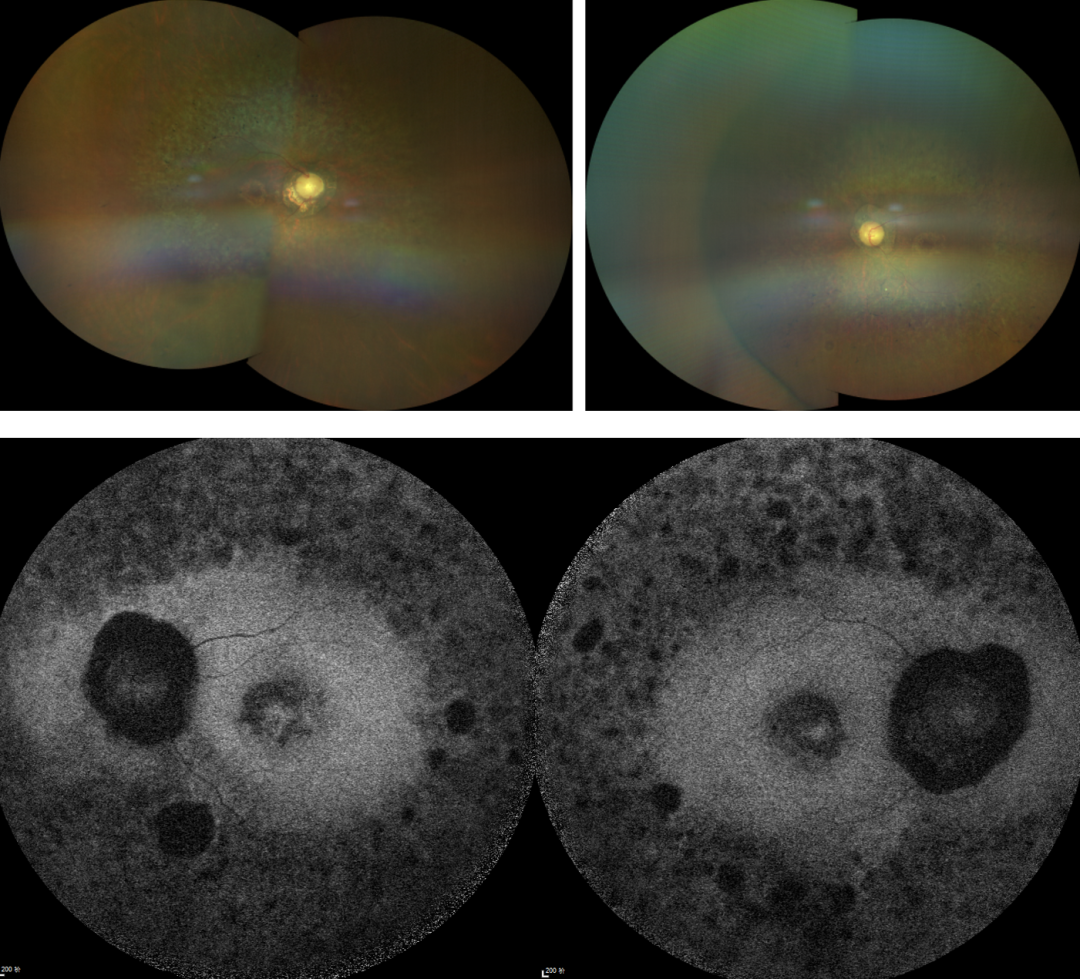

RP的診斷主要依靠眼底檢查、視野檢查、視網(wǎng)膜電圖(ERG)和基因檢測。眼底檢查可見典型的"骨細胞樣"色素沉著,ERG顯示視網(wǎng)膜功能下降,基因檢測可確定具體的突變基因。